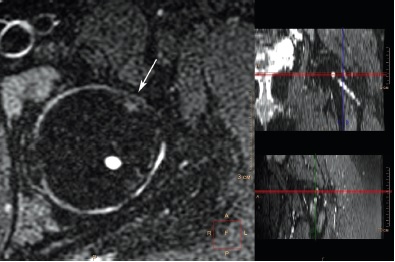

При анализе МРТ, выполненной на 19-м году жизни, установлено, что вышеописанная деформация перехода «головка – шейка» различной выраженности присутствовала в 25 (78,1%) из 32 суставов со смещением эпифиза, величина передневерхнего угла α при этом варьировала в диапазоне от 46° до 71°, в среднем 60,6±7,7° (рис. 3, 4).

Рис. 3. МРТ левого тазобедренного сустава пациентки 18 лет 2 мес. через 4 года 7 мес. после операции, косая аксиальная проекция, Т2-взвешенное изображение. Деформация перехода «головка – шейка» (обозначена стрелкой) — отсутствие нормальной вогнутости перехода и увеличенный передневерхний угол α — 87,4 °

Рис. 4. МРТ левого тазобедренного сустава пациента 18 лет 7 мес. через 5 лет 2 мес. после операции, радиальный срез на уровне перехода «головка – шейка», перпендикулярный оси шейки бедренной кости, Т2-взвешенное изображение). Деформация перехода «головка – шейка» (обозначена стрелкой) — избыток костной массы в передневерхней части перехода, нарушающий сферичность головки бедренной кости

Фиброцисты в наших наблюдениях отчетливо визуализировались в 8 (25,0%) из 32 суставов со смещением эпифиза, величина передневерхнего угла α в каждом из этих 8 суставов превышала 55° (рис. 5).

Рис. 5. МРТ левого тазобедренного сустава пациентки 18 лет 4 мес. через 4 года 5 мес. после операции, аксиальная проекция, режим с жироподавлением. Фиброциста (обозначена стрелкой), локализующаяся у передневерхнего края шейки бедренной кости на краю суставной поверхности, в месте столкновения